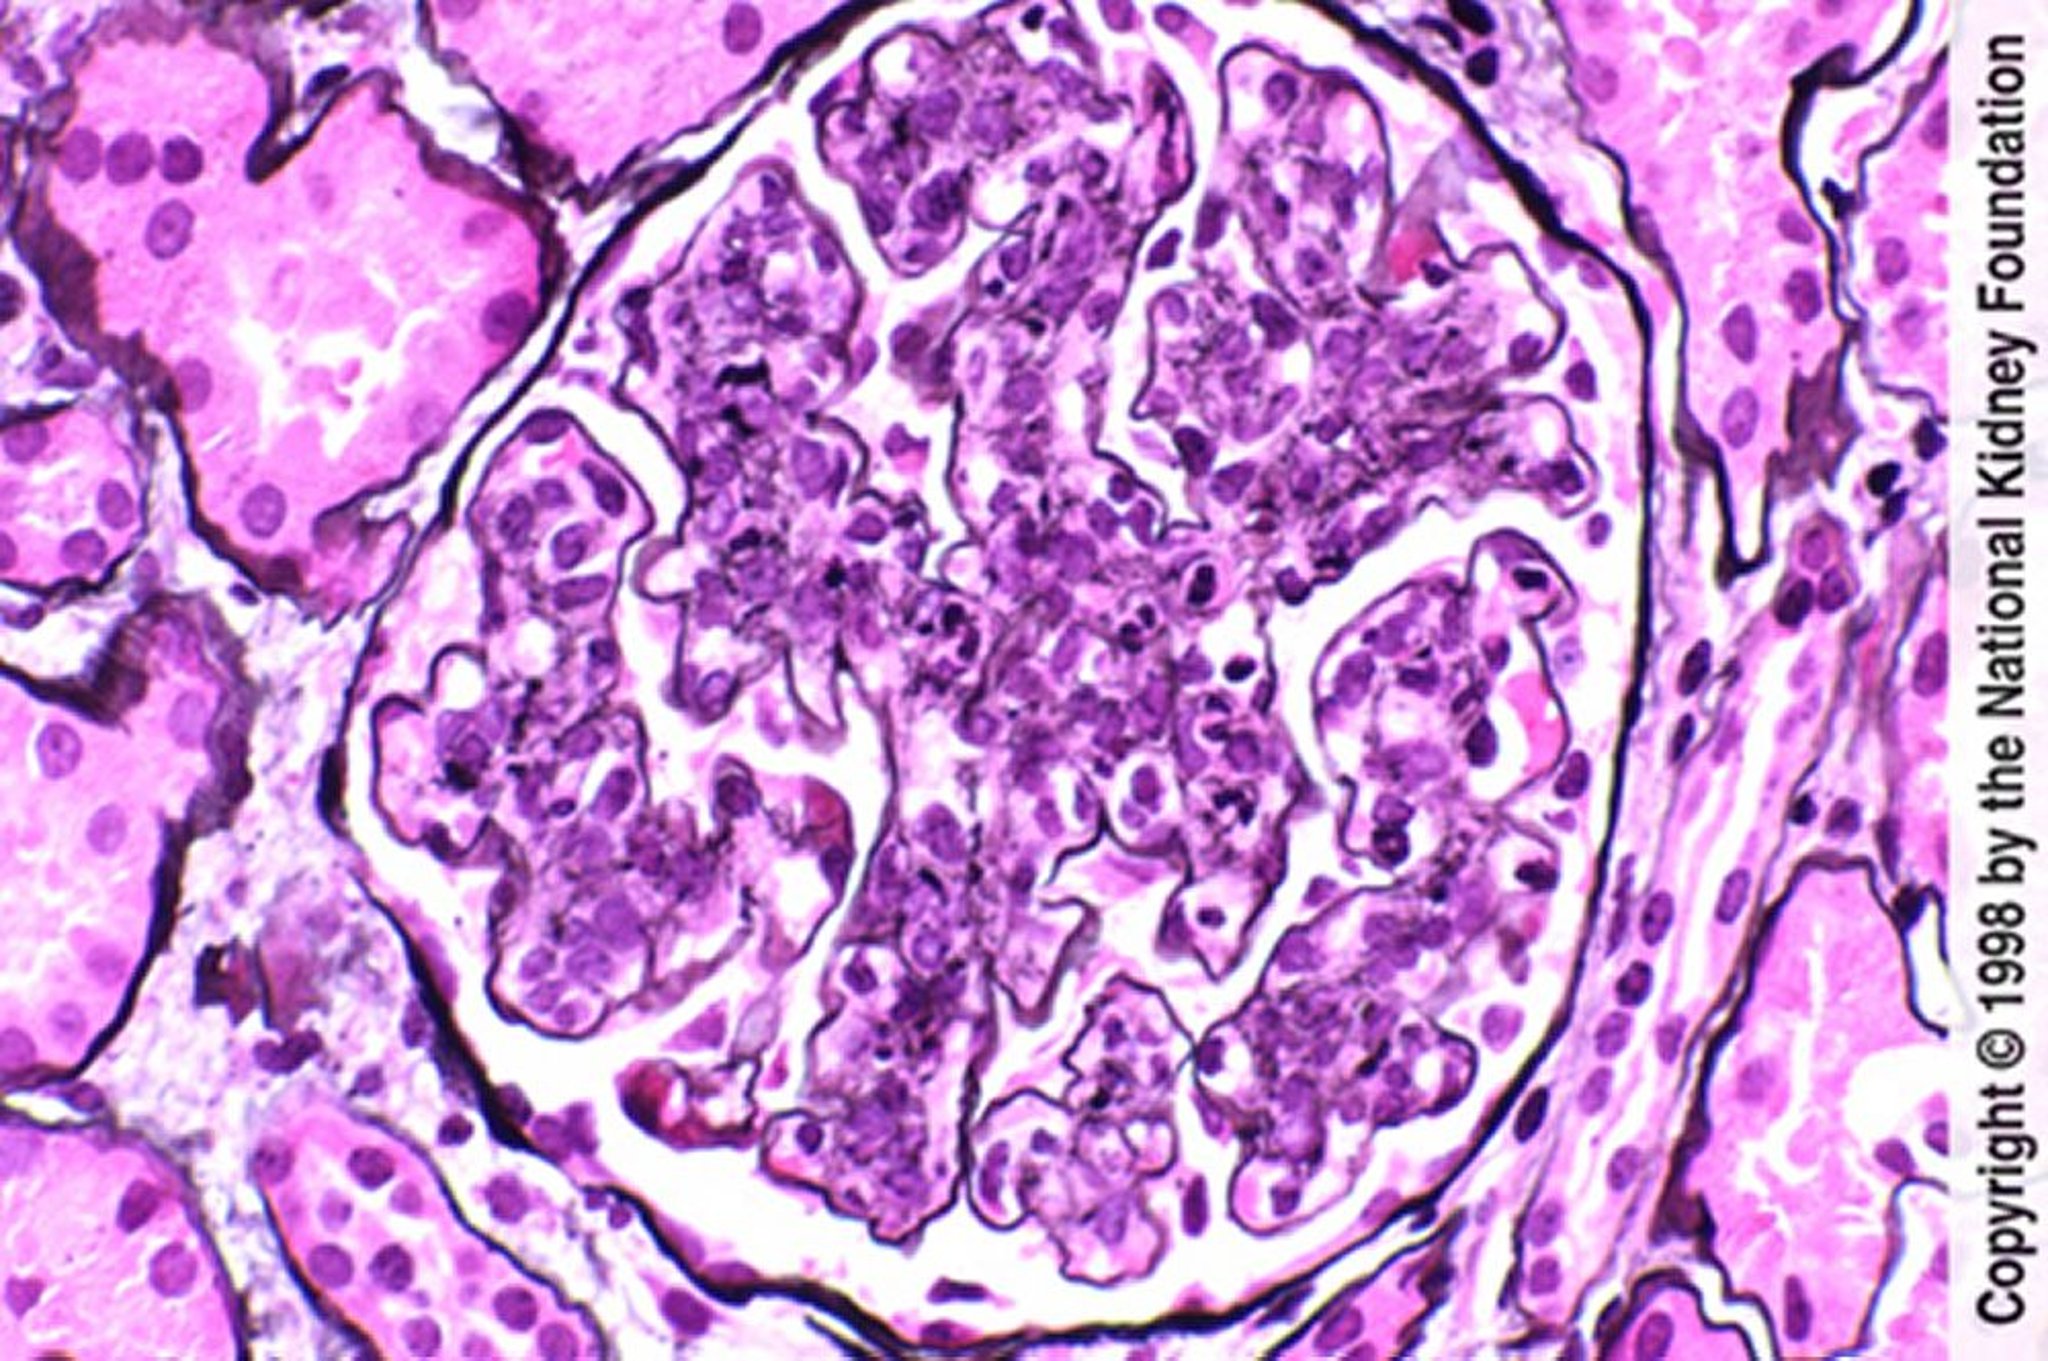

Постінфекційний гломерулонефрит (гіперклітинність з нейтрофільною інфільтрацією)

Endothelial and mesangial hypercellularity with neutrophilic infiltration (Jones silver stain, ×400).

Image provided by Agnes Fogo, MD, and the American Journal of Kidney Diseases' Atlas of Renal Pathology (see www.ajkd.org).